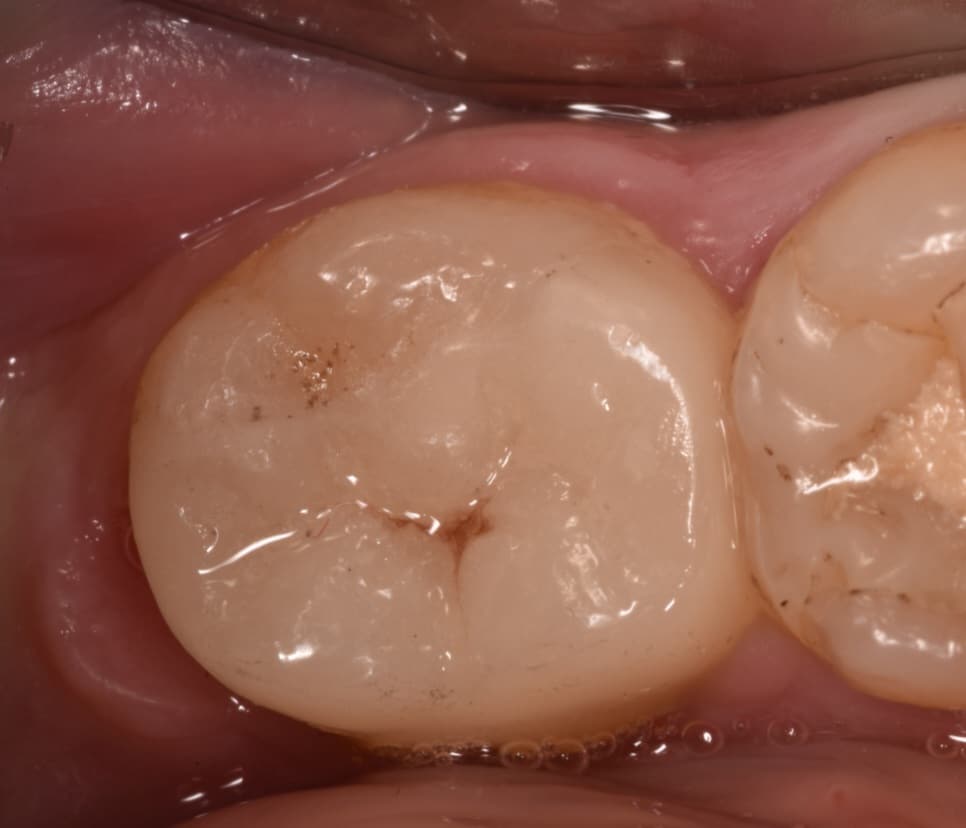

Patient came to clinic asking to restor her lower wisdom tooth

3.5 months follow up